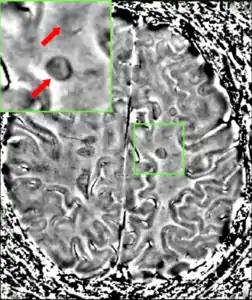

• Lesions – A classic method in which a brain-region of interest is naturally or intentionally destroyed to observe any resulting changes such as degraded or enhanced performance on some behavioral measure. Lesions can be placed with relatively high accuracy "Thanks to a variety of brain 'atlases' which provide a map of brain regions in 3-dimensional "stereotactic coordinates.

The part of the picture emphasized shows the lesion in the brain. This type of lesion can be removed through surgery.